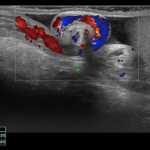

Let's hop into April with a discussion of hip ultrasound-- DDH and hip effusion.

Here is a nice intro about how to measure the angles on a hip ultrasound.

And another that nicely delineates the anatomy.